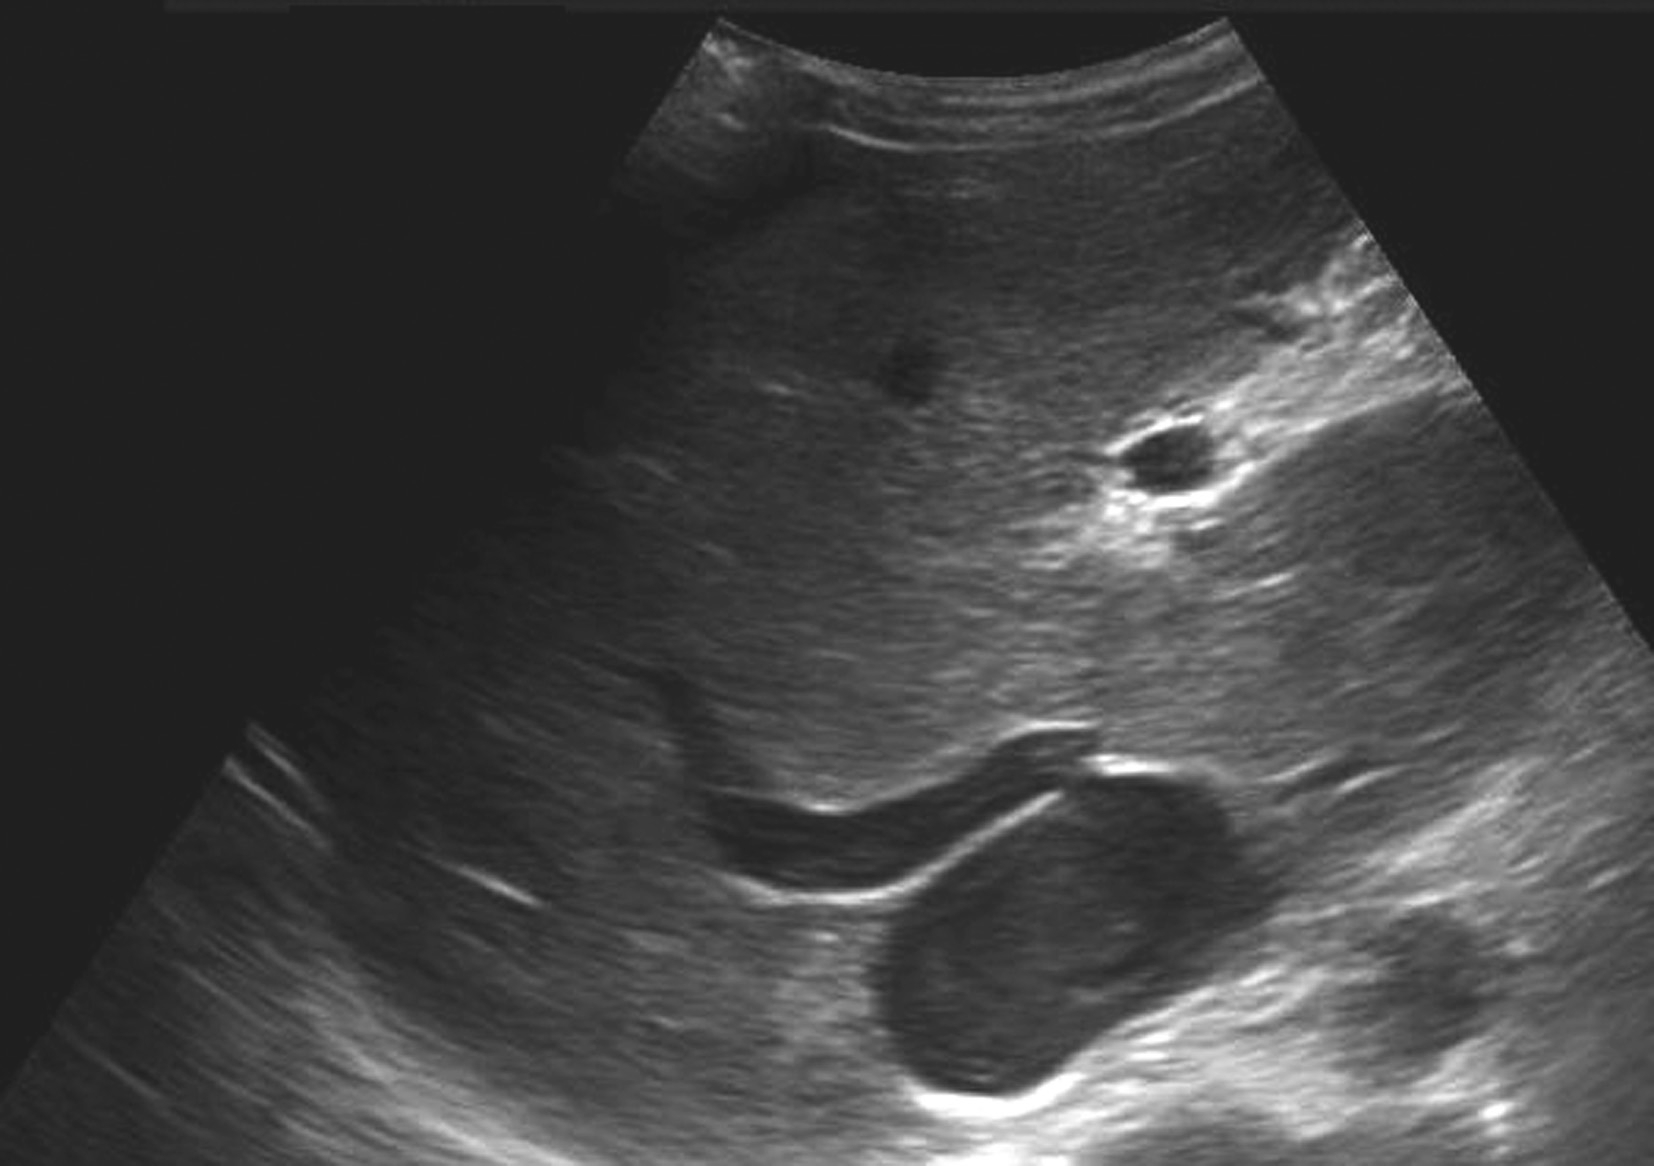

【声像图表现】

(1)灰阶超声:

肝门区结构紊乱,肝外门静脉周围或管腔内可见多条弯曲成团的血管,呈蜂窝状或网格状无回声区结构,在结构紊乱的肝门部仔细辨认可见管腔狭窄、壁增厚回声增强的门静脉管道,管腔内可见癌栓或血栓,部分可压迫胆道系统造成肝内外胆管扩张。可出现继发门静脉高压声像图改变,如脾肿大、脾静脉及肠系膜上静脉增宽,严重者可见腹水。